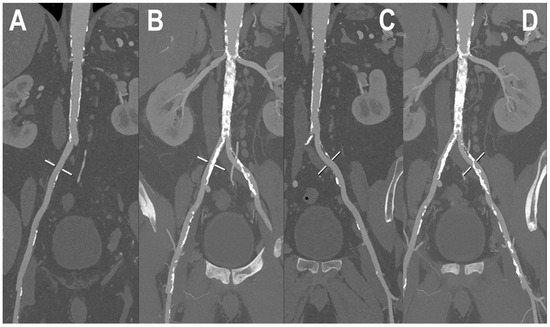

- Euler, A.; Higashigaito, K.; Mergen, V.; Sartoretti, T.; Zanini, B.; Schmidt, B.; Flohr, T.G.; Ulzheimer, S.; Eberhard, M.; Alkadhi, H. High-Pitch Photon-Counting Detector Computed Tomography Angiography of the Aorta: Intraindividual Comparison to Energy-Integrating Detector Computed Tomography at Equal Radiation Dose. Investig. Radiol. 2022, 57, 115–121. [Google Scholar] [CrossRef]

- Higashigaito, K.; Mergen, V.; Eberhard, M.; Jungblut, L.; Hebeisen, M.; Rätzer, S.; Zanini, B.; Kobe, A.; Martini, K.; Euler, A.; et al. CT Angiography of the Aorta Using Photon-counting Detector CT with Reduced Contrast Media Volume. Radiol. Cardiothorac. Imaging 2023, 5, e220140. [Google Scholar] [CrossRef] [PubMed]

| Higashigaito et al. [48] | 2022 | In vivo (human) | 39 | Aorta | PCCT with reconstructions of VMI at 40, 50, and 60 keV showed a significantly increased CNR at similar image quality compared to EID-CT at identical radiation dose. |

| Euler et al. [49] | 2022 | In vivo (human) | 40 | Aorta | Compared with EID-CT at matched radiation dose, PCCT angiography of the aorta with VMI at 40 and 45 keV resulted in a significant increase of CNR. The CNR gain was higher in overweight patients. |

| Higashigaito et al. [50] | 2023 | In vivo (human) | 100 | Aorta | Angiography of the aorta with PCCT was associated with higher CNR compared to conventional CT. PCCT with a low-volume contrast media protocol gave comparable image quality to that of EID-CT at the same radiation dose. |